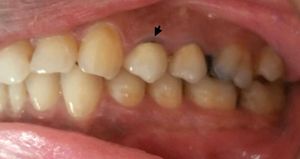

레진 결합 가공의치 (Resin-bonded bridge)Resin-bonded bridge영어는 폰틱 측면에 있는 유지 "윙"을 사용하여 지대치 치아의 에칭된 법랑질(치아의 가장 바깥쪽 표면)에 부착하는 방식이다. '메릴랜드 브릿지'라고도 불린다. 지대치 치아는 준비가 거의 또는 전혀 필요하지 않다. 지대치 치아가 온전하고 튼튼할 때(예: 크라운 또는 주요 충전물이 없을 때) 가장 자주 사용된다.[4] 단일 유지 캔틸레버 레진 결합 가교는 양쪽에 유지 윙이 있는 엔드 투 엔드 레진 결합 가교보다 합병증이 적다.[4]

레진 결합 가공의치 (Resin-bonded bridge): Resin-bonded bridge영어는 폰틱 측면에 있는 유지 "윙"을 사용하여 지대치 치아의 에칭된 법랑질에 부착하는 방식이다. '메릴랜드 브릿지'라고도 불린다. 지대치 치아는 준비가 거의 또는 전혀 필요하지 않다. 지대치 치아가 온전하고 튼튼할 때(예: 크라운 또는 주요 충전물이 없을 때) 가장 자주 사용된다.[4] 단일 유지 캔틸레버 레진 결합 가교는 양쪽에 유지 윙이 있는 엔드 투 엔드 레진 결합 가교보다 합병증이 적다.[4]